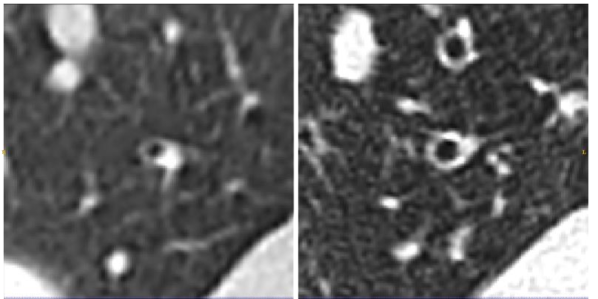

3.2 CT Reconstruction

On a subset of images, four patients were scanned using the Toshiba Aquilion One Scanner. On the same scan, two different images were computed. The images were reconstructed using the Lung and Body kernels respectively. An example of the reconstruction kernels is displayed on Figure 3. We acquired the airway segmentation and distal point from a single reconstruction kernel as described in Table 1. The tapering measurement was computed on both reconstruction kernels using the same airway segmentation and distal points. We used the same airways as described in Table LABEL:table_of_airways.

Refer to caption

Figure 3: Images from the same CT scan with the body kernel (LEFT) and lung kernel (RIGHT). Both images are displayed in the same intensity window.